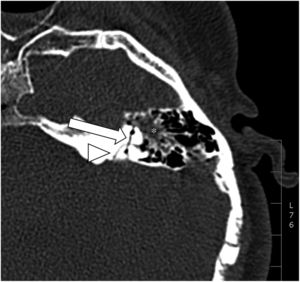

Facial nerveFacial nerve injury occurs in 5–10% of temporal bone fractures, and the portion most commonly affected is the geniculate ganglion3,4,7,8,14,21,22 (Fig. 7). The facial nerve canal has to be examined along its entire length in the axial plane, using oblique sagittal reconstructions to assess the integrity and continuity of the tympanic and mastoid segments in a single image.3

Immediate post-traumatic onset of symptoms usually indicates a serious injury to the facial nerve, by transection or compression by a bone fragment, and may indicate the need for urgent surgical exploration. In contrast, delayed symptom onset, i.e. 1–16 days after the injury, usually occurs due to oedema, swelling or intra- or peri-neural haematoma, and can be managed with observation and corticosteroids, considering surgical exploration if there is a clear bone fragment invading the facial canal.3–5,10,14